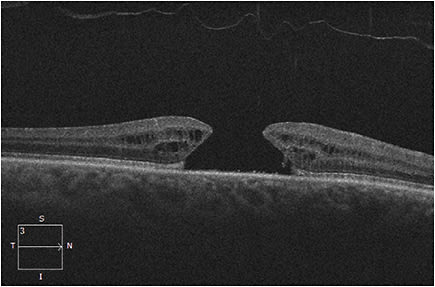

The optical cross section of the retina that OCT provides makes this technology invaluable in helping to differentiate a pseudo-hole from a true macular hole (Figure 9).

Figure 9. Left: Lamellar macular hole. Right: Full-thickness macular hole.

You can observe patients with a lamellar macular hole, as the natural history of lamellar macular holes trend towards long-term stable visual acuity, generally without requiring surgical intervention. However, refer a full-thickness macular hole to a retinal specialist for management, as they frequently need surgical intervention for macular hole closure with pars plana vitrectomy and membrane peel, if medical therapy fails. The chronicity and size of a full-thickness macular hole can influence surgical success of macular hole closure rates, thus these patients benefit from early referral to a retinal specialist.